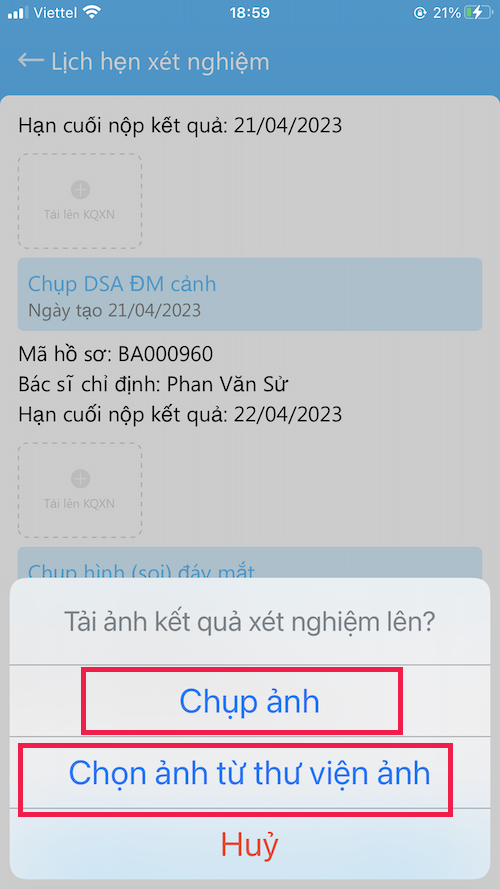

GỞI XÉT NGHIỆM

Gởi xét nghiệm cho Bác sĩ

- Vào Tài khoản –> Lịch hẹn xét nghiệm

- Kết quả gởi bằng hình ảnh (chụp trực tiếp hoặc lấy từ thư viện)

- Nên làm theo đúng thời gian hẹn

- Có kết quả, Bác sĩ sẽ gởi toa thuốc

- Vì lý do nào đó, bệnh nhân không làm xét nghiệm, hãy gởi cho bác sĩ nội dung lý do chưa làm (chụp hình chữ viết)

- Bấm Gửi kết quả xét nghiệm khi đã tải hình kết quả lên

- Các xét nghiệm nên trao đổi với Bác sĩ khi khám bệnh

GỞI XÉT NGHIỆM

Gởi xét nghiệm cho Bác sĩ

- Vào Tài khoản –> Lịch hẹn xét nghiệm

- Kết quả gởi bằng hình ảnh (chụp trực tiếp hoặc lấy từ thư viện)

- Nên làm theo đúng thời gian hẹn

- Có kết quả, Bác sĩ sẽ gởi toa thuốc

- Vì lý do nào đó, bệnh nhân không làm xét nghiệm, hãy gởi cho bác sĩ nội dung lý do chưa làm (chụp hình chữ viết)

- Bấm Gửi kết quả xét nghiệm khi đã tải hình kết quả lên

- Các xét nghiệm nên trao đổi với Bác sĩ khi khám bệnh

GỞI XÉT NGHIỆM

Gởi xét nghiệm cho Bác sĩ

- Kết quả gởi bằng hình ảnh (chụp trực tiếp hoặc lấy từ thư viện)

Một kết quả xét nghiệm có thể có nhiều hình

(1) Hình 1

(2) Hình gởi lên tiếp

- Nên làm theo đúng thời gian hẹn

- Có kết quả, Bác sĩ sẽ gởi toa thuốc

- Bấm Gửi kết quả xét nghiệm khi đã tải hình kết quả lên

- Các xét nghiệm nên trao đổi với Bác sĩ khi khám bệnh